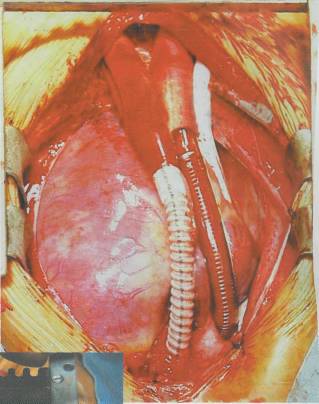

Tüm damar yapılarını da içeren üç boyutlu kalın bir karaciğer oluşturma fikri 5-6 yıl öncesine kadar yalnızca bir hayal olarak kabul ediliyordu. Dr. Vacanti'nin 1997 yılında bir farenin sırtında insan kulağı geliştirdiği günden beri, üç boyutlu ve damarlı yapay karaciğer fikri hayal olmaktan çıktı. Harvard Üniversitesi'ndeki bilim

adamları orijinal karaciğer benzeri bir model oluşturdular. Yapay karaciğer yaratmada en önemli basamak, karmaşık damar yapısını oluşturmak. Bu nedenle ilk olarak, vücuttan çıkartılmış bir karaciğerin damarlarının içine, özel bir sıvı plastik materyal enjekte ediliyor. Bu sıvı kısa süre içinde katılaşarak damarların şeklini alıyor. Daha sonra karaciğer dokusu özel sıvılarla eritilerek yok ediliyor. Geriye yalnızca katılaşmış ve damar şeklini almış olan madde kalıyor. Kurumuş ağaç dallarına benzeyen bu yapı, karaciğerin damar yapısını temsil ediyor. Bu yapının görüntüleri bilgisayara aktarılarak üç boyutlu görüntüler elde ediliyor. Bu görüntüler yardımıyla silikon kalıplar hazırlanıyor. Silikon kalıpların içine polilaktik glikolik asit (PLGA) yapısındaki bir madde dökülüyor. Böylece karaciğer

damarlarının organik bir iskeleti oluşturuluyor. Bu iskeleti oluşturduktan sonraki aşamaysa hücrelerin oluşturulması. Damar iskeleti çevresine yerleştirilen karaciğer hücreleri, belirli büyüme faktörleri yardımıyla çoğalarak organın kalın etli kısmını oluşturuyorlar. Bir sonraki aşamaysa damarın oluşturulması. Bunun için süngerimsi yapıda olan PLGA içine damar hücreleri enjekte ediliyor. İskelet, hücrelerin çoğalması için gerekli büyüme faktörlerini ve besin maddelerini içeriyor. Damar hücreleri iskelet boyunca ilerleyerek karaciğer hücrelerine yapışıyor. Burada çoğalan damar hücreleri, iskelet çevresinde birleşerek tam bir damar yapısı oluşturuyorlar. PLGA iskelet birkaç ay içinde kendiliğinden eriyerek geride karaciğer hücreleri ve içinde damarları olan yapay bir organ bırakıyor. Bu şekilde oluşturulan yapay karaciğer hayvanlarda denendi. Oldukça iyi kan akımının sağlandığı bu organlarda dışarı kan sızıntısı da gözlenmedi.